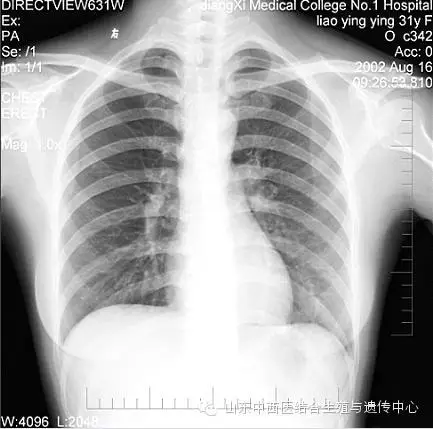

不知道怀孕,做了X线、CT怎么办?美国:孕期X线检查指南 (转载)